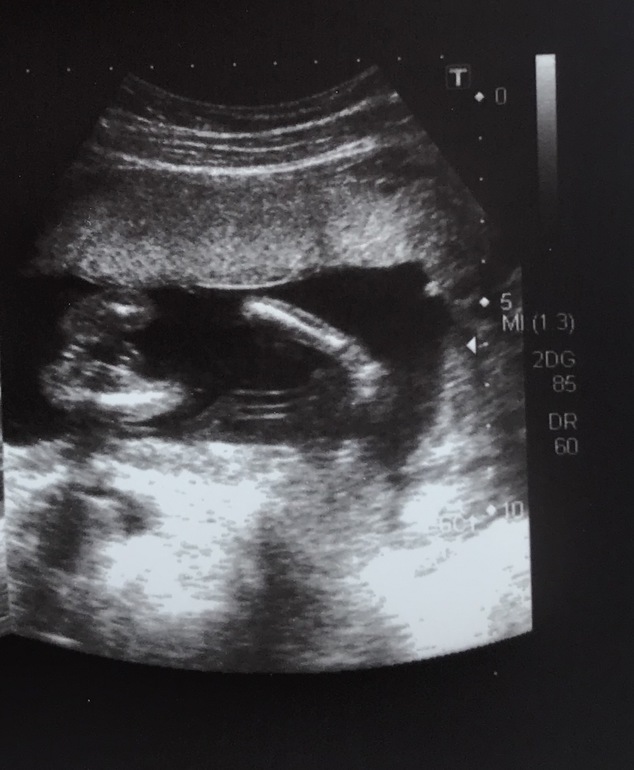

Вопросы про УЗИ, обследования и анализы: что, где, как, когда?Девочки , гляньте кто это у нас )))?

У нас так же. 2 белые полосочки....половые губы. Девчулька-красотулька. Поздравляю с принцессой

Я девочку вижу, пирожочек) с сыном у нас прям краник такой значительный был, а тут нету краника 😁

Две ягодицы , и между ними как пирожок , и вон рука или нога попала )) фото снизу ракурс как будто на стекло села 🤣🤣🤣ну вы поняли

не понимаю, как здесь ребенка можно увидеть.